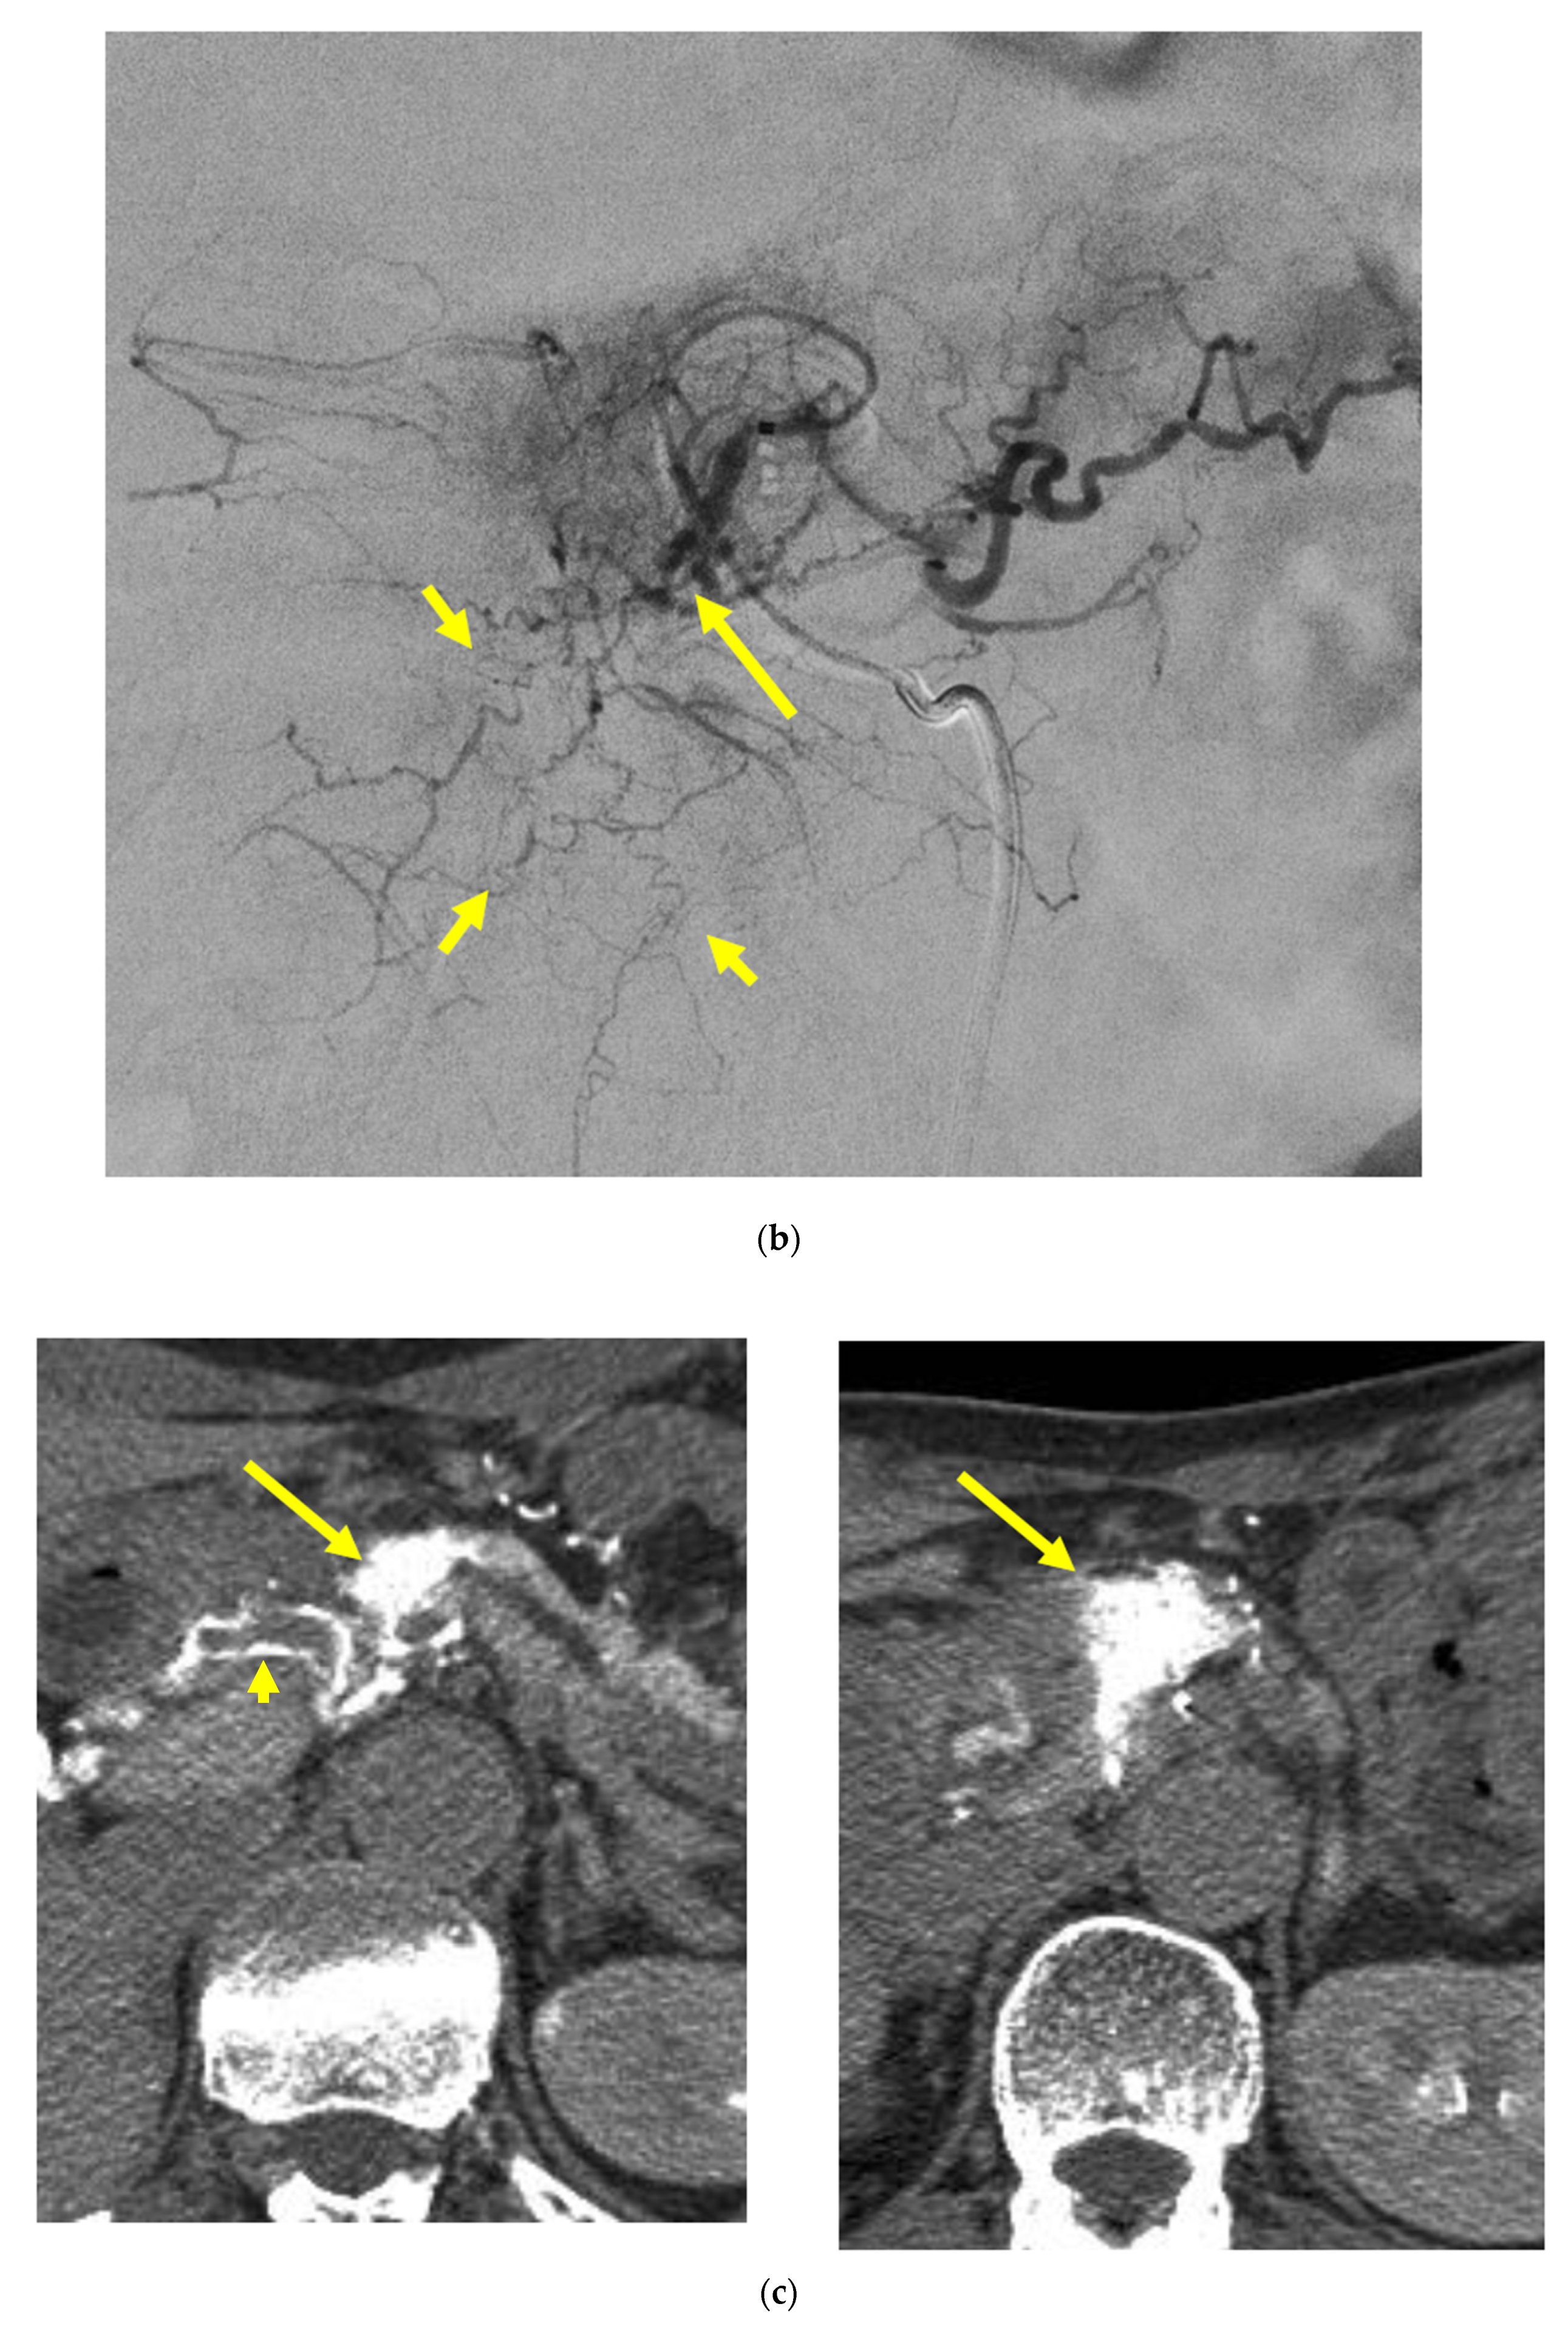

Identifying Supplying Arteries to Pancreatic Cancer

Method of Arterial Administration of Anticancer Agents

2.5.1. Judging Completeness or Incompleteness of Arterial Administration of Chemotherapeutic Agents